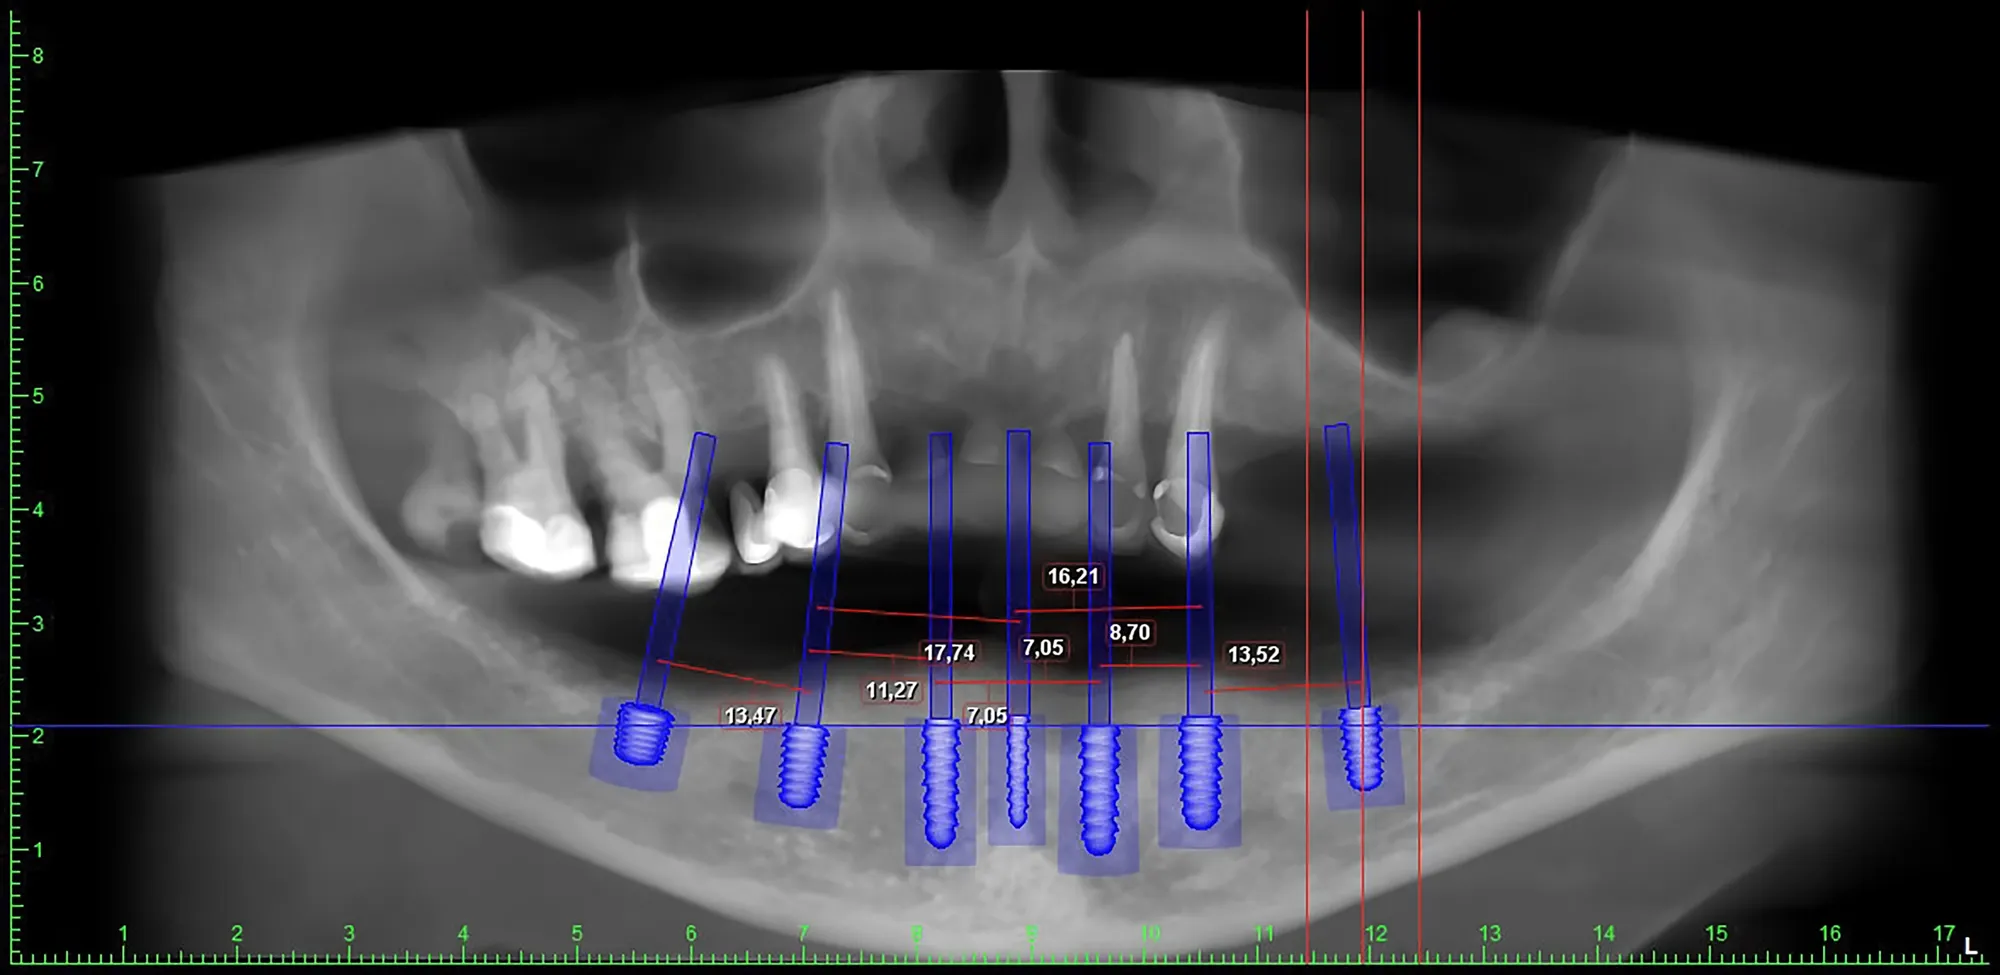

Lo scanner intraorale consente di rilevare immagini 3D ad alta definizione della bocca, eliminando la necessità di impronte tradizionali con paste fastidiose. Questa tecnologia permette una pianificazione più accurata dei trattamenti ortodontici, protesici e implantari, migliorando la precisione e il comfort del paziente.